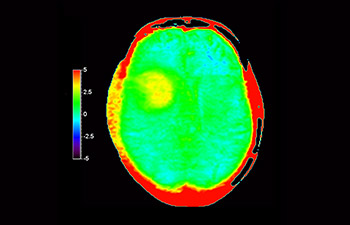

En una sociedad con una alta incidencia de trastornos neurológicos, Philips se compromete a ofrecer una excelente asistencia en el tratamiento y claridad en el diagnóstico para todos los pacientes. Hoy en día, aunque la RM es la modalidad de referencia para la adquisición de imágenes de neurooncología, su precisión a la hora de clasificar los tumores y de evaluar el seguimiento de los tratamientos aún tiene mucho margen de mejora. 3D APT (Amide Proton Transfer, transferencia de protones de amidas) es un exclusivo método de adquisición de imágenes por RM cerebral sin contraste que tiene por objetivo ofrecer un diagnóstico de neurooncología más fiable. 3D APT utiliza la presencia de proteínas celulares endógenas para producir una señal de RM que se corresponde directamente con la proliferación celular, que es un marcador de la actividad tumoral. 3D APT puede ayudar a los profesionales de la salud debidamente instruidos a diferenciar los gliomas de baja malignidad de los gliomas más graves, así como a diferenciar la progresión tumoral del efecto del tratamiento1.

con 3D APT